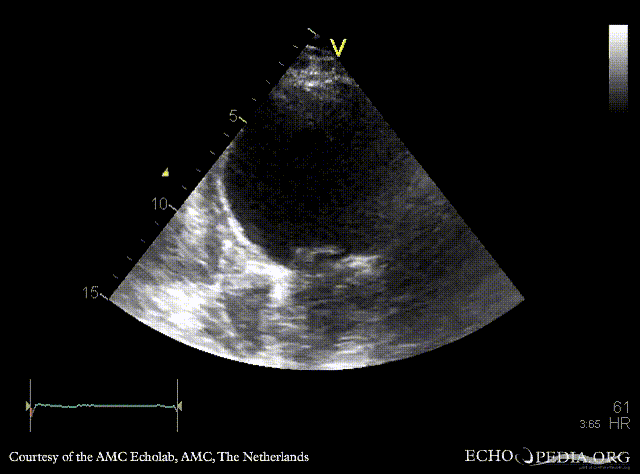

E00707.gif E00708.gif

A4CH: dilated left ventricle, poor function, akinesia of inferoseptal wall A2CH: dilated left ventricle, poor function, akinesia of inferior wall